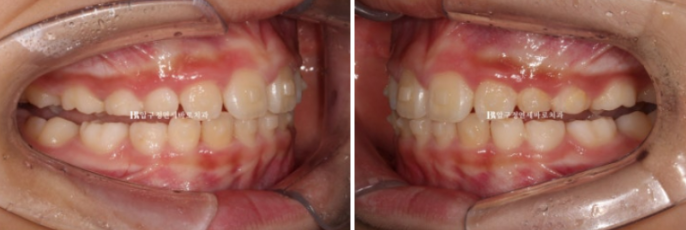

24.02

MA치료 6개월차, 중간에 찍은 사진입니다.

MA 치료단계에서는 앞니가 먼저 닿고 어금니가 떠 있습니다.

과정상 불가피하게 일어나는 부분입니다.

이 부분은 MA 치료 후반부에 어금니쪽 장치를 잘라서 끼면 자연스럽게 다시 닿게 됩니다.